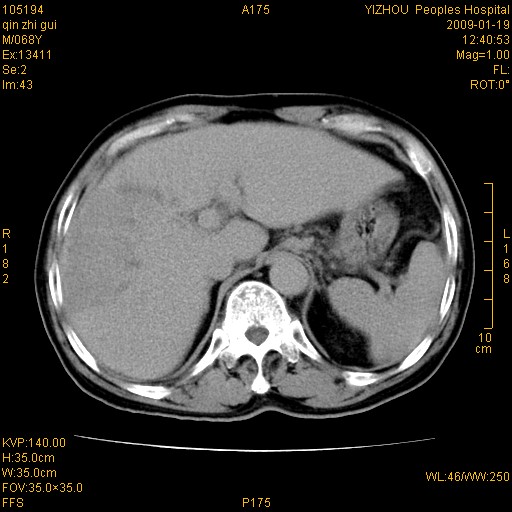

以下是引用随光逐影在2009-1-21 16:11:00的发言:[br]1)考虑肝右叶肝癌并肝静脉及门静脉瘤栓形成。2)肝硬化,少量腹水。3)胆囊炎。4)右侧少量胸腔积液。

病灶外缘凹凸不平,平扫低密度,增强动脉期有强化,门脉早显,静脉期及延期呈延迟强化,结合病史考虑右肝前叶巨块型肝癌可能性大,强化表现不除外胆管细胞癌